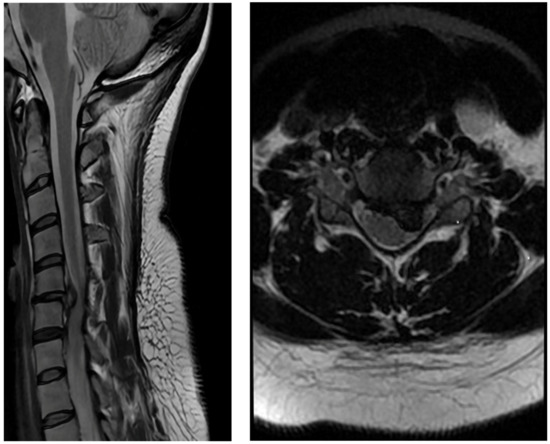

Figure 1.

Preoperative MRI scan showing a large, herniated disc with spinal cord compression.